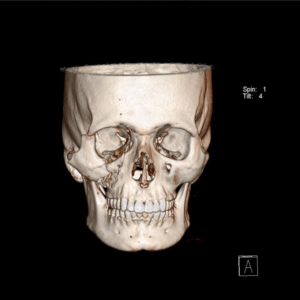

O diagnóstico é feito pelo exame físico dos ferimentos e, nos casos de suspeita de fratura, deve se associar radiografias e tomografias computadorizadas. Esse avaliação poderá ser feita no hospital (se o paciente estiver internado) ou no consultório odontológico. O primeiro passo no tratamento é garantir a vida do paciente. O profissional deve garantir que o paciente esteja respirando bem e sem lesões graves que podem levar a morte rapidamente (como hemorragias severas, obstrução de vias aéreas e lesões de órgãos vitais)